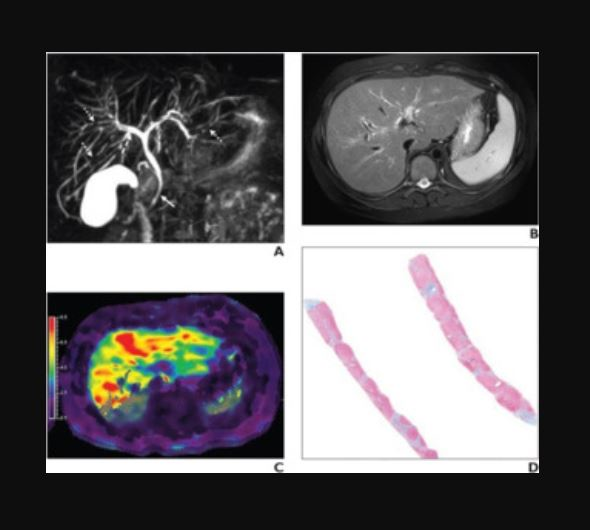

Imaging findings on MRI can help clinicians understand a tumor's "biological behavior" and thus improve their ability to make an accurate prognosis regarding disease recurrence, the group explained: Features such as ill-defined tumor margins, an absence of a tumor capsule, and enhancement of the area around the tumor the arterial phase may indicate that the cancer is aggressive.

"Diffusion-weighted imaging is an important MRI functional imaging tool with the unique ability to display microscopic functional information such as the tissue cell structure and cell membrane integrity, and its quantitative parameters can provide information on the status of a lesion after treatment," the authors noted.

The group conducted a study that included 339 patients treated for liver cancer with percutaneous microwave ablation between January 2014 and December 2017. All patients underwent multiparametric MRI. The researchers included the following factors in the algorithm they developed:

- Ill-defined tumor margins

- Lack of tumor capsule enhancement

- Preablative apparent diffusion coefficient (ADC)

- Changes in ADC (ΔADC)

- Exponential ADC